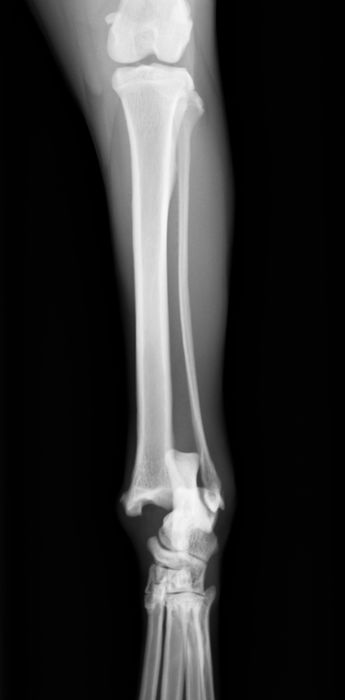

骨折・脱臼治療における最小侵襲手術(MIS)について

骨折治療における最小侵襲手術(minimally invasive surgery MIS)

MISは、人医療では20年以上前から提唱されているコンセプトですが、軟部組織(皮膚や筋肉など)の侵襲を最小限にし、骨折部に対してもよけいな侵襲を加えないことで骨折治癒を促進させる方法です。近年、獣医療領域でも実施されるようになってきました。

当院では、症例に応じて創外固定法によるMISや最小侵襲骨接合術(minimum invasive plate osteosynthesis MIPO)を実施しています。

※単純骨折に対するプレート固定はopen reduction internal fixationを行っています。